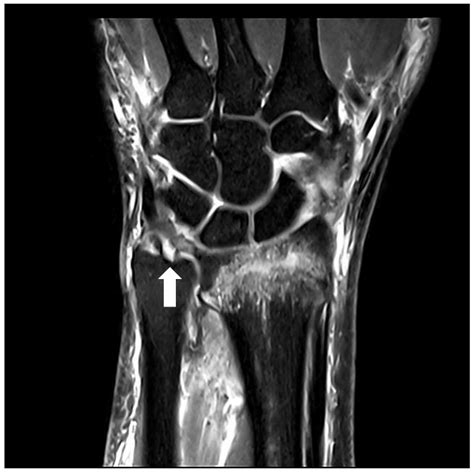

• Imaging Tests: X-rays, MRI, or CT scans may be ordered to visualize the knee joint and confirm the diagnosis. MRI is particularly useful for detecting soft tissue injuries like cartilage tears.